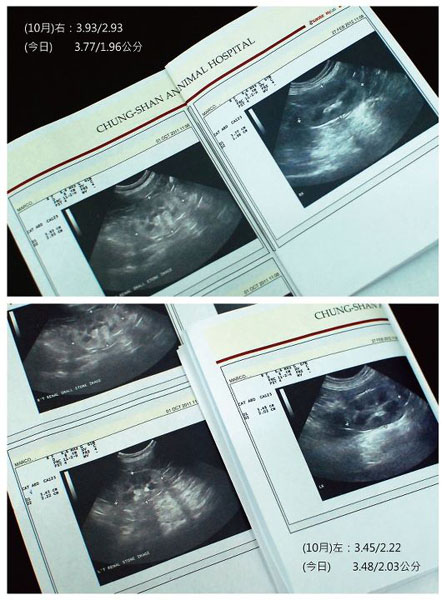

呼~還好結石都有縮小,心裡鬆懈不少